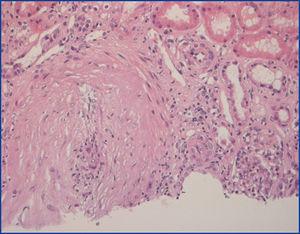

Varón de 70 años con antecedentes de asma bronquial que ingresa por infiltrados pulmonares, eosinofilia y p-ANCA 1/160 MPO. Se diagnostica de SCS y se inicia prednisona 1 mg/kg/día. A los 20 días presenta deterioro de la función renal, microhematuria sin proteinuria, hipertensión arterial y elevación de p-ANCA 1/1320. Se realiza biopsia renal percutánea, observándose glomérulos sin alteraciones significativas y una arteria de mediano calibre con necrosis fibrinoide e infiltración de neutrófilos transparietal, intenso infiltrado inflamatorio linfoplasmocitario intersticial con abundantes eosinófilos (figura 1). Con inmunofluorescencia directa (IFD) se detectan depósitos vasculares de IgG, IgM, C3, C4 y C1q.

Figura 1. Primera biopsia renal (H-E).